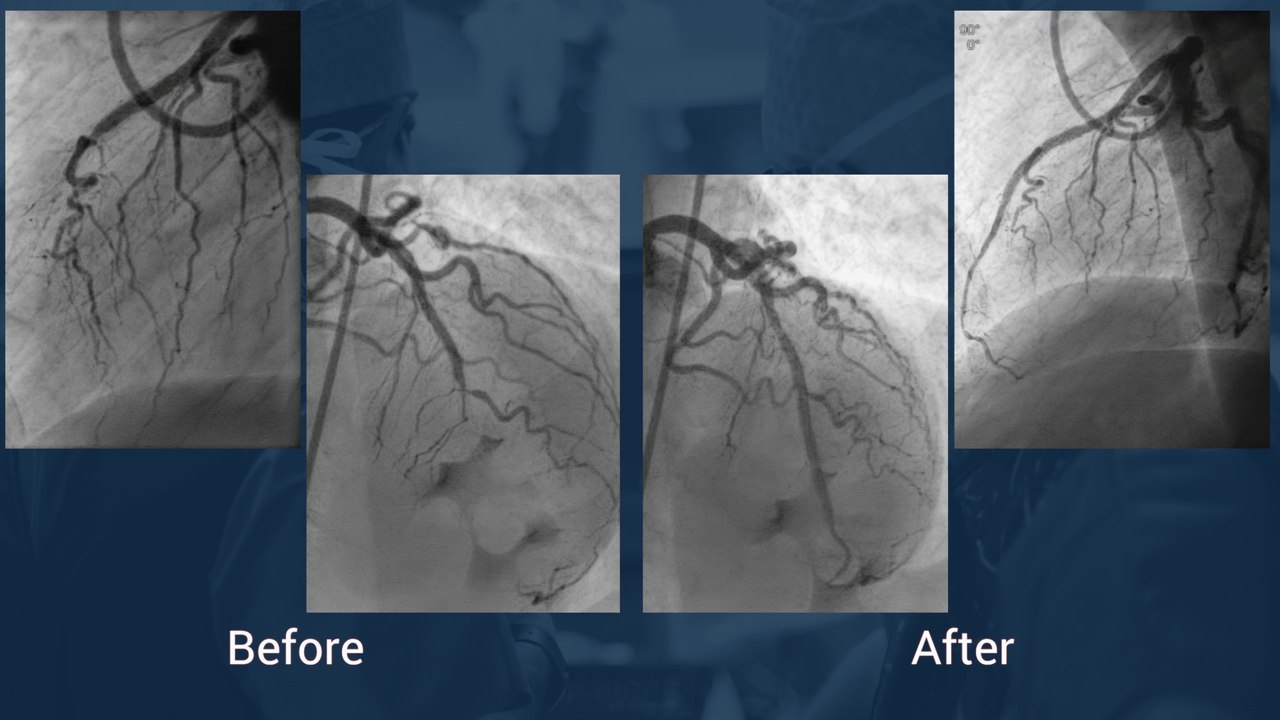

High risk left main PCI supported by IABP

Rotational atherectomy and complex bifurcation stenting